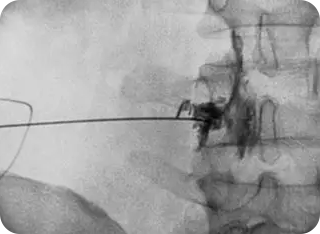

신경성형술(PEN)

가느다란 특수 카테터를 삽입해 유착된 신경을 풀어주고 약물을 주입하는 방식입니다.

절개 없이 진행되며, 만성 통증 환자에게 효과적입니다.

• #척추·관절 고주파 열치료

• #수핵성형술

• #섬유륜성형술